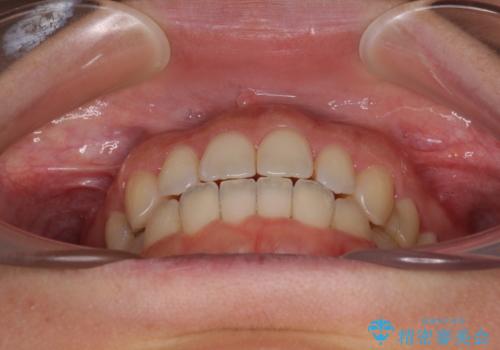

【モニター】オープンバイトをインビザライン矯正で治す

- 前歯の開咬を気にして来院された患者様です。

開咬の治療は、前歯を閉じるように動かすとともに、上下臼歯を圧下(骨内にめり込ませる)させることで進めて行きます。

インビザラインは臼歯の圧下を効果的に行えるため、インビザラインを用いて矯正治療を行うこととしました。